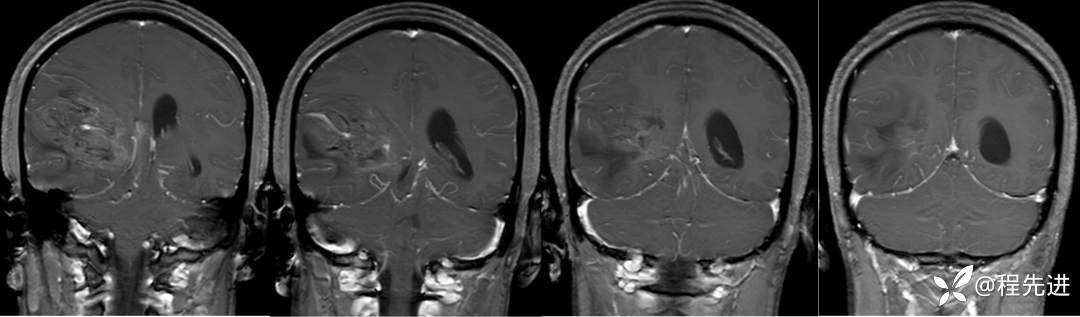

T1+C: